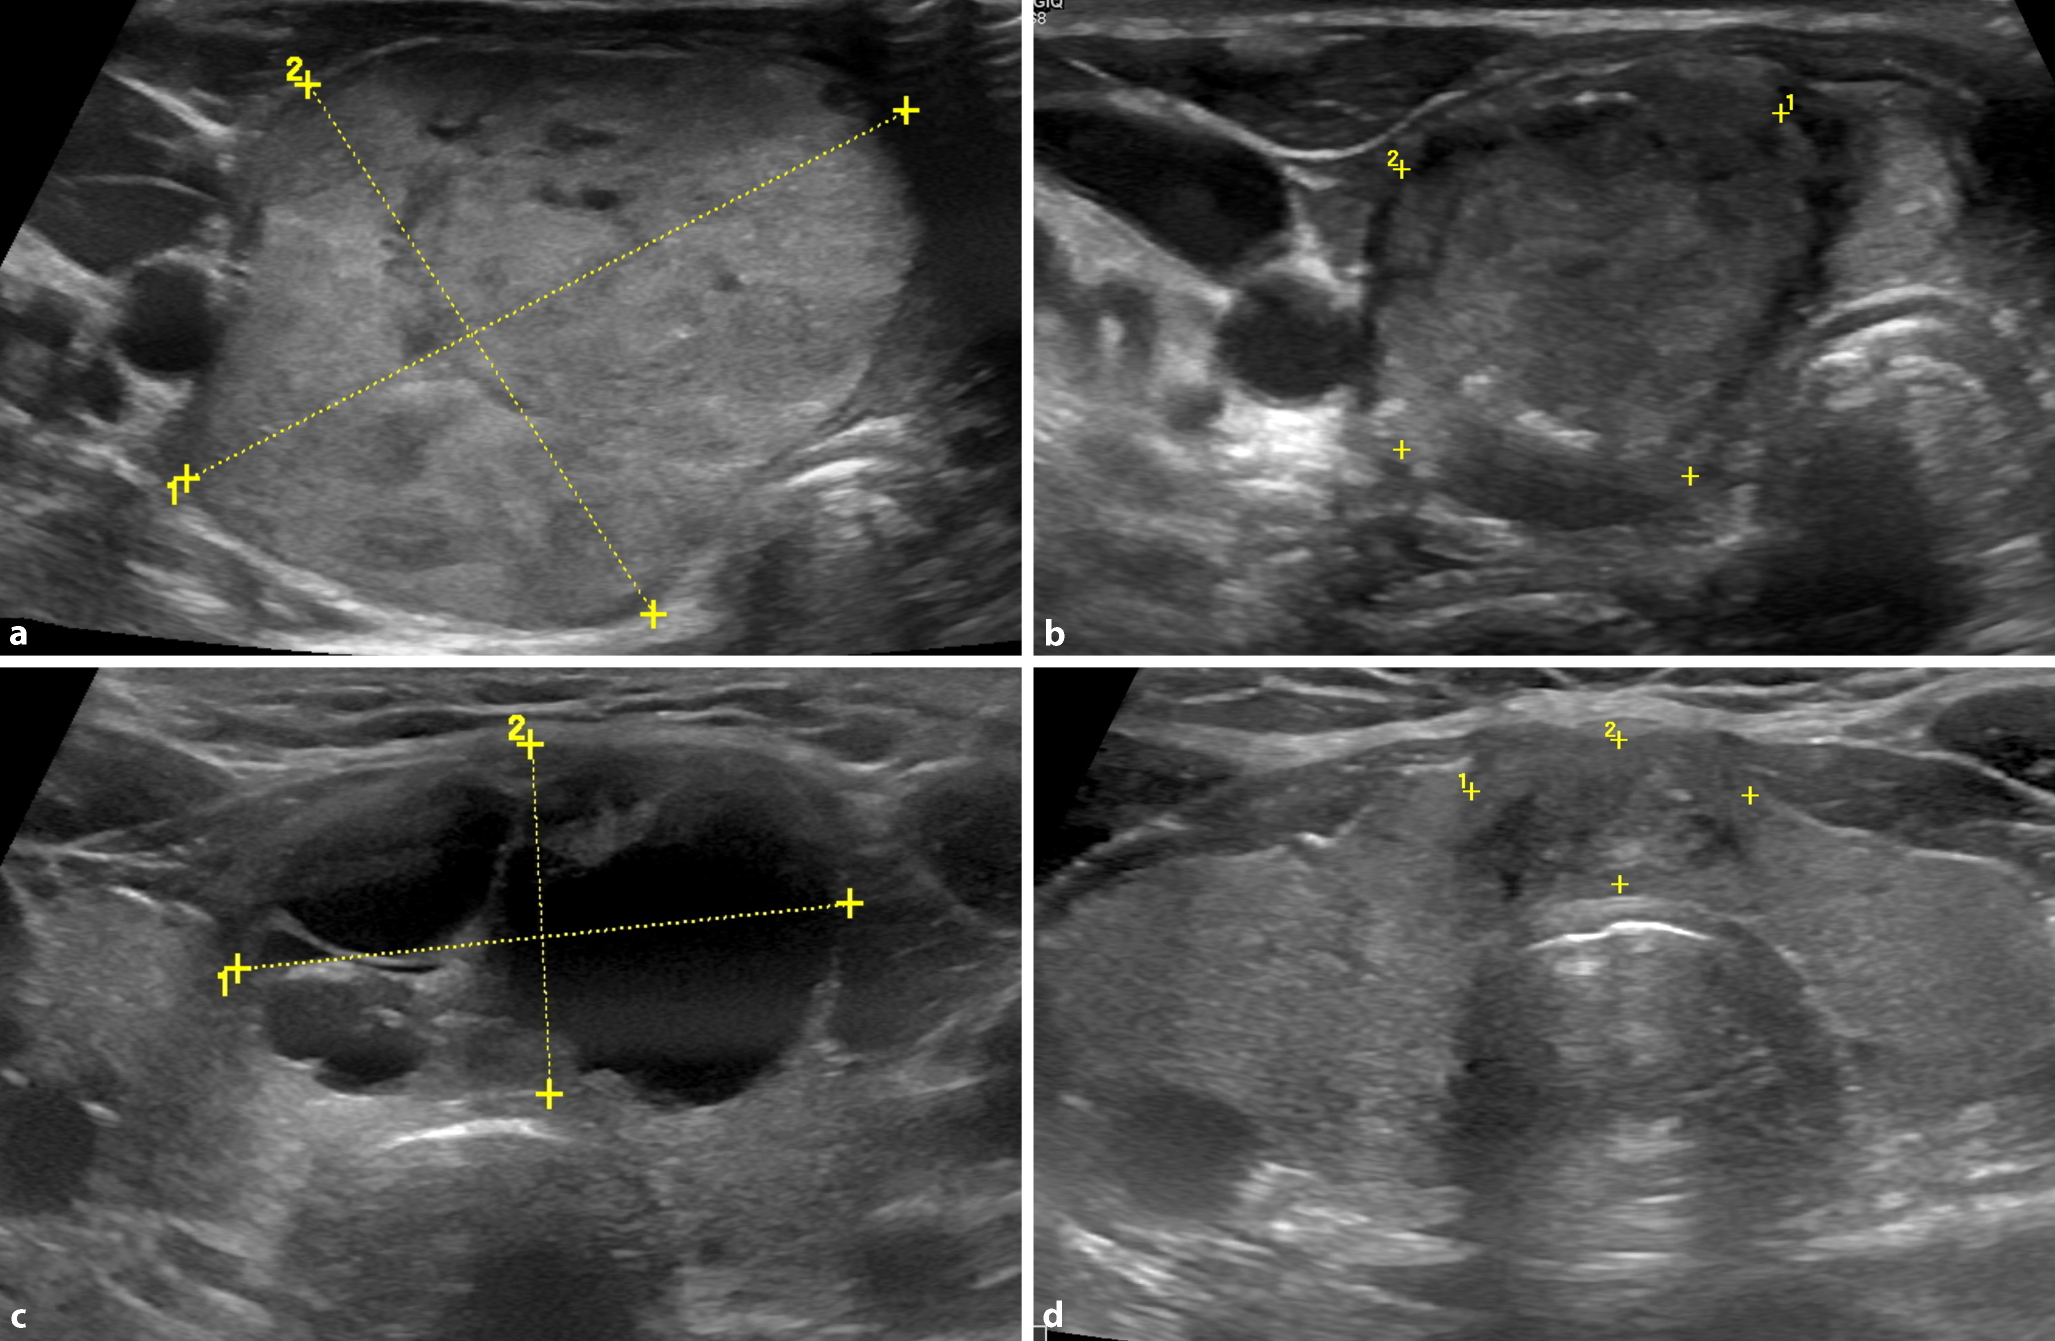

Abb. 2

a und b Beispiel einer Radiofrequenzablation (RFA) eines soliden Knotens vor und 12 Mon. nach der Behandlung. a 50-jährige Patientin, 5‑facher Volumenzuwachs des Knotens in 8 Jahren, mehrfache Operationsempfehlung, visuell der Knoten deutlich sichtbar, Symptomatikscore 4 von 10; Knotenvolumen: 40 ml. b Nach 12 Monaten der Knoten nur noch palpabel, Symptomatikscore 0, Knotenvolumen 8,2 ml (−80 %). Dieses Beispiel zeigt auch, dass das exakte Setzen der Messmarken, die sich an der initial längsten Querachse orientieren, wichtig ist für die Erfassung des Verlaufs des Knotenvolumens. c und d Beispiel einer RFA eines zystischen Kolloidknotens. c Prätracheales, kompensiertes zystisches autonomes Adenom, hochvisköser Inhalt, Knotenvolumen 10,6 ml, TSH 0,6 uU/ml, Symptomatikscore 4 (von 10), visueller Knotenscore 3 (von 3), Operation empfohlen. d Nach 12 Monaten visueller und Symptomatikscore 0, transformiertes Knotenrestgewebe 1,2 ml (−89 %), TSH 1,0 uU/ml